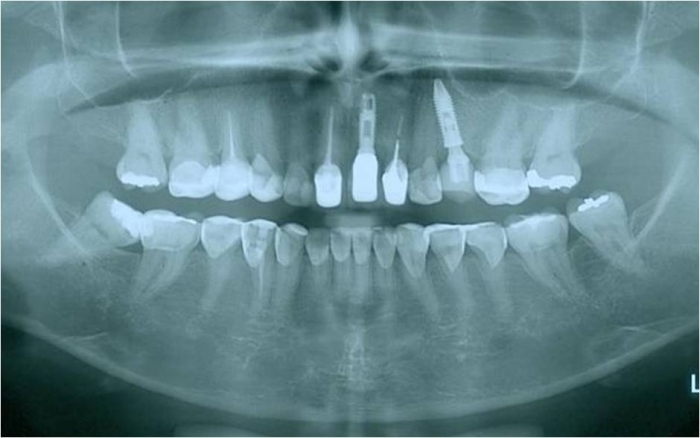

Raio X inicial com fratura radicular do dente 24